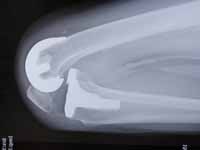

全人工膝関節置換術 / TKA

変形性膝関節症が高度で50~80歳の方では全人工膝関節(Totak Knee Arthroplasty; TKA)が薦められます。

最新ジンマー社製TKA Personaを用いています。心臓や重度の糖尿病がなければ80歳まで問題ありません。

人工関節の耐用年数は20~30年ありますので50歳を過ぎれば手術は可能です。

X線写真